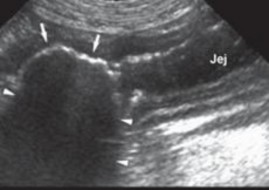

Siêu âm đóng vai trò quan trọng trong chẩn đoán bệnh viêm tử cung, các phát hiện siêu âm điển hình phù hợp với viêm tử cung bao gồm chứng to tử cung, thành tử cung dày lên, thay đổi tăng sinh nội mạc tử cung, sừng tử cung hình ống xoắn do chất lỏng gây ra, và giảm âm vang trong lòng tử cung chứa dịch. Siêu âm có thể phân biệt viêm tử cung với các mô mềm khác, khiến tử cung căng lên và là điều bắt buộc để đánh giá về sự hiện diện của tăng sản nội mạc tử cung và sự nguyên vẹn của nội mạc tử cung (Nyland & Mattoon, 2002; Wallace & Casal, 2018). Tương tự nghiên cứu Hagman (2018) khi sử dụng siêu âm để chẩn đoán bệnh viêm tử cung và tăng sản nội mạc tử cung, trên chó mắc tăng sản nội mạc tử cung quan sát thấy thành tử cung dày lên và có các cấu trúc nang không cản âm và không có dịch trong tử cung, trong khi đó với trường hợp chó vừa bị viêm tử cung và tăng sản nội mạc tử cung quan sát thấy thấy thành tử cung dày lên và có các cấu trúc nang không cản âm và quan sát dịch trong tử cung. Tương tự nghiên cứu Mattei & cs. (2018) khi thực hiện chẩn đoán trên một chó Labrador Retriever 7 tuổi chưa sinh sản được đưa đi viện vì tiền sử nôn mửa, chán ăn trong 1 ngày, đi tiểu nhiều, khát nước nhẹ và có dấu hiệu mệt mỏi, sưng âm hộ với một ít lượng dịch màu vàng. Chụp X quang bụng cho thấy một khối giãn nở chủ yếu chứa đầy khí, ban đầu nghi ngờ có tắc ruột non. Sau khi kiểm tra siêu âm phát hiện một bên sừng tử cung có vách giảm âm đồng nhất và chứa khí và chất lỏng có độ

vang trong lòng ống và chẩn đoán viêm tử cung. Siêu âm có thể được sử dụng như một phương pháp chẩn đoán không đưa vào bên trong cơ thể để phân biệt tắc ruột và tử viêm cung khí thũng.

Hình 4.25. Hình ảnh siêu âm tử cung bị viêm của giống Poodle 5 tuổi

(mũi tên)